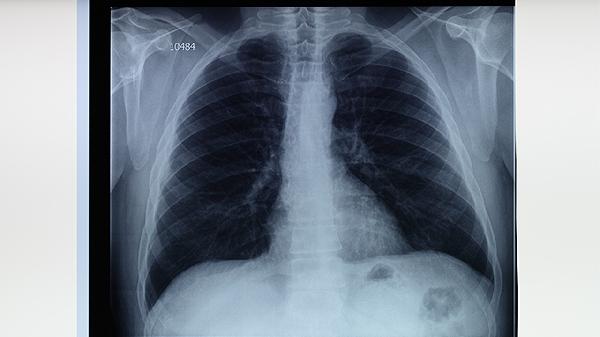

肺结核潜伏期通常为2至12周,但可能长达数年,具体时间取决于个体免疫状态和感染程度。潜伏期内无明显症状,但可通过结核菌素试验或干扰素释放试验检测感染情况。

肺结核潜伏期是指从结核分枝杆菌感染到出现临床症状的时间。免疫系统功能是影响潜伏期长短的关键因素。免疫功能较强的人群,潜伏期可能较长,甚至终身不发病;免疫功能较弱者,潜伏期较短,可能迅速发展为活动性结核病。年龄、营养状况、慢性疾病(如糖尿病、艾滋病)等也会影响潜伏期。

4.潜伏期与活动性结核病的区别

潜伏性结核感染与活动性结核病的主要区别在于症状和传染性。潜伏期患者无明显症状,且不具传染性;活动性结核病患者常出现咳嗽、发热、盗汗、体重下降等症状,且可通过飞沫传播。早期识别潜伏性感染并进行干预,是控制结核病传播的关键。